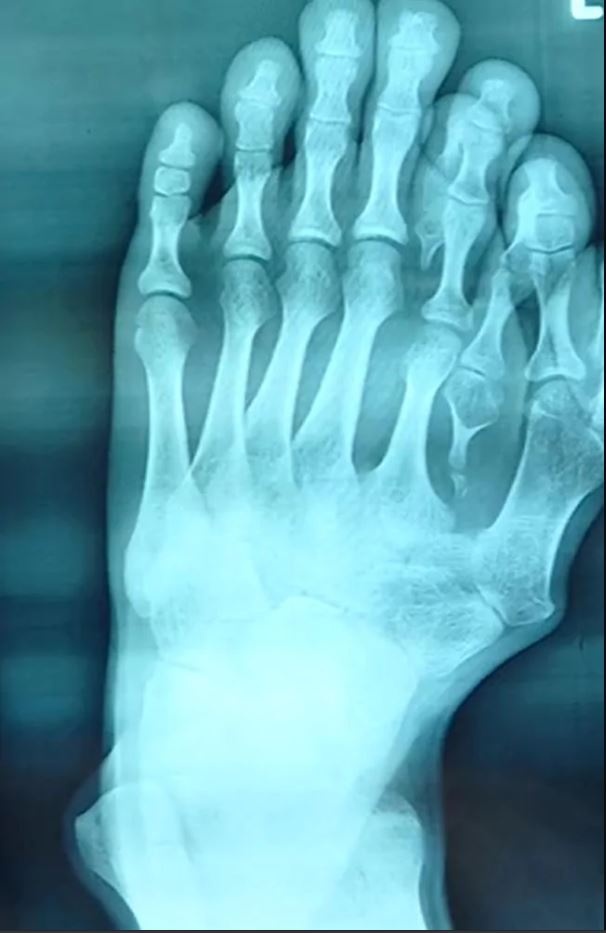

| Bàn chân 9 ngón của Ajun trước khi phẫu thuật. Ảnh: Fox News. |

Năm 10 tuổi, Ajun ý thức được ngón chân kỳ lạ của mình nên đã bỏ thói quen đi dép. Từ đó đến nay, cậu trung thành với đôi giày nhằm che giấu bàn chân 9 ngón. Tổng cộng, hai bàn chân của Ajun có 14 ngón.

Trước đây, cậu không phẫu thuật vì cha mẹ tin rằng 9 là con số may mắn. 9 ngón chân của Ajun là “do trời ban”. Khi con sinh ra với đôi chân khác thường, cha mẹ đã đến gặp thầy bói thay vì bác sĩ để xin lời khuyên.